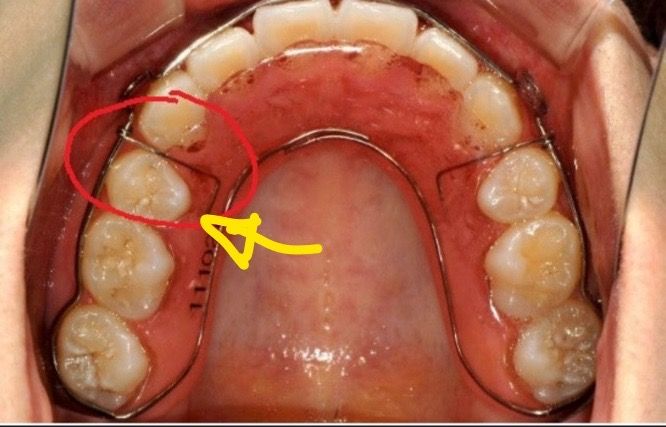

고정식유지장치 제거후 여기에 틈이 생겼는데 괜찮을까요..?ㅠㅠㅠ들뜨는 건 없는데 제거한 후 틈이 생겨 버려가지고 틀어질까봐 무서워서요,,분명 제거 후 가철식 끼었을 때 의사쌤도 봤을텐데..그럼 괜찮은 건가요??ㅠㅠㅠ답변 부탁드리겠습니다!!

• 1번 째 사진

저정도 틈이 생긴건 크게 문제가 되진 않을것같습니다. 유지장치가 잘 맞으면 크게 걱정하지 않으셔도 됩니다.

유지장치는 치아의 위치를 고정해 주기 위해서 제작을 하게 됩니다. 사진으로 보이는 틈은 크게 문제가 되지 않을 가능성이 높습니다.

자세한 확인을 위해서 치과에서 진료를 받아보는 것을 권유드립니다.

고정식유지장치 제거후 여기에 틈이 생겼는데 괜찮을까요. -> 유지장치 탈착이 스무스하게 잘 되고, 앞니쪽 철사만 변형이 없다면 치열 유지 기능에는 문제없는 상태로 보입니다